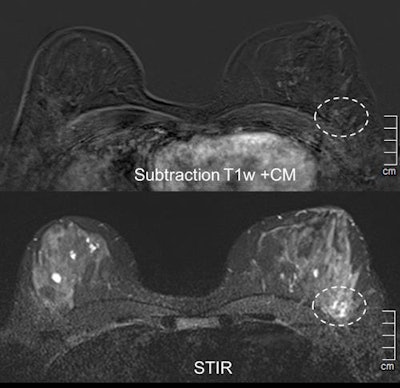

Case 2: A 47-year-old woman with new palpable finding in the left lateral breast with architectural distortion in ultrasound, no suspicious microcalcifications. Problem-solving MRI showed no enhancement in the indicated region, thereby excluding malignancy. STIR = short tau inversion recovery.He added that breast MRI required more stringent justification when it came to reimbursement issues. In Germany, insurance is paid on a case-by-case basis after written request, whereas in Austria, MR is fully integrated in the screening program and is fully reimbursed in clinical routine when used as an extra imaging technique.